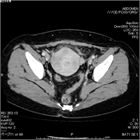

1. 下腹部痛・発熱・炎症反応上昇・膿瘍など画像所見・原因病原体の検出をもって診断する。